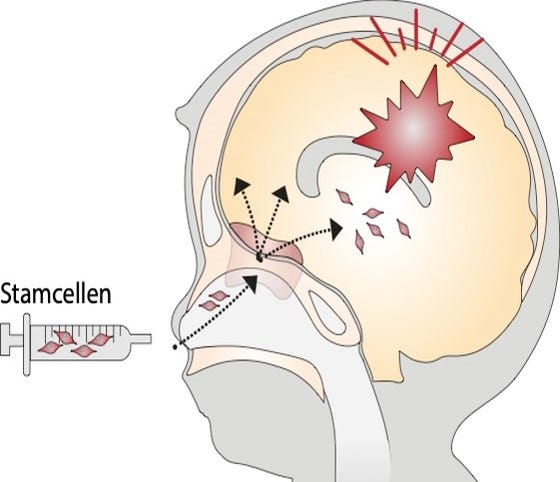

Illustration of intranasal application of mesenchymal stem cells to support endogenous neuroregeneration after neonatal brain injury.

At present, one of our key focus points is developing intranasal mesenchymal stem cell (MSC) therapy from bench-to-bedside for neonatal brain injury. We study the migration of MSCs from the nose into damaged brain lesions, we focus on optimization strategies for cell-based therapy, and we explore mechanisms of neurorepair and stimulation of endogenous stem cell niches. Our previous research in this field has led to the first-in-human clinical trial in which safety of intranasal MSC application in term neonates with perinatal stroke has been explored (PASSIoN). We are currently also developing this therapy for encephalopathy of prematurity in animal models for fetal inflammation and fetal growth restriction.